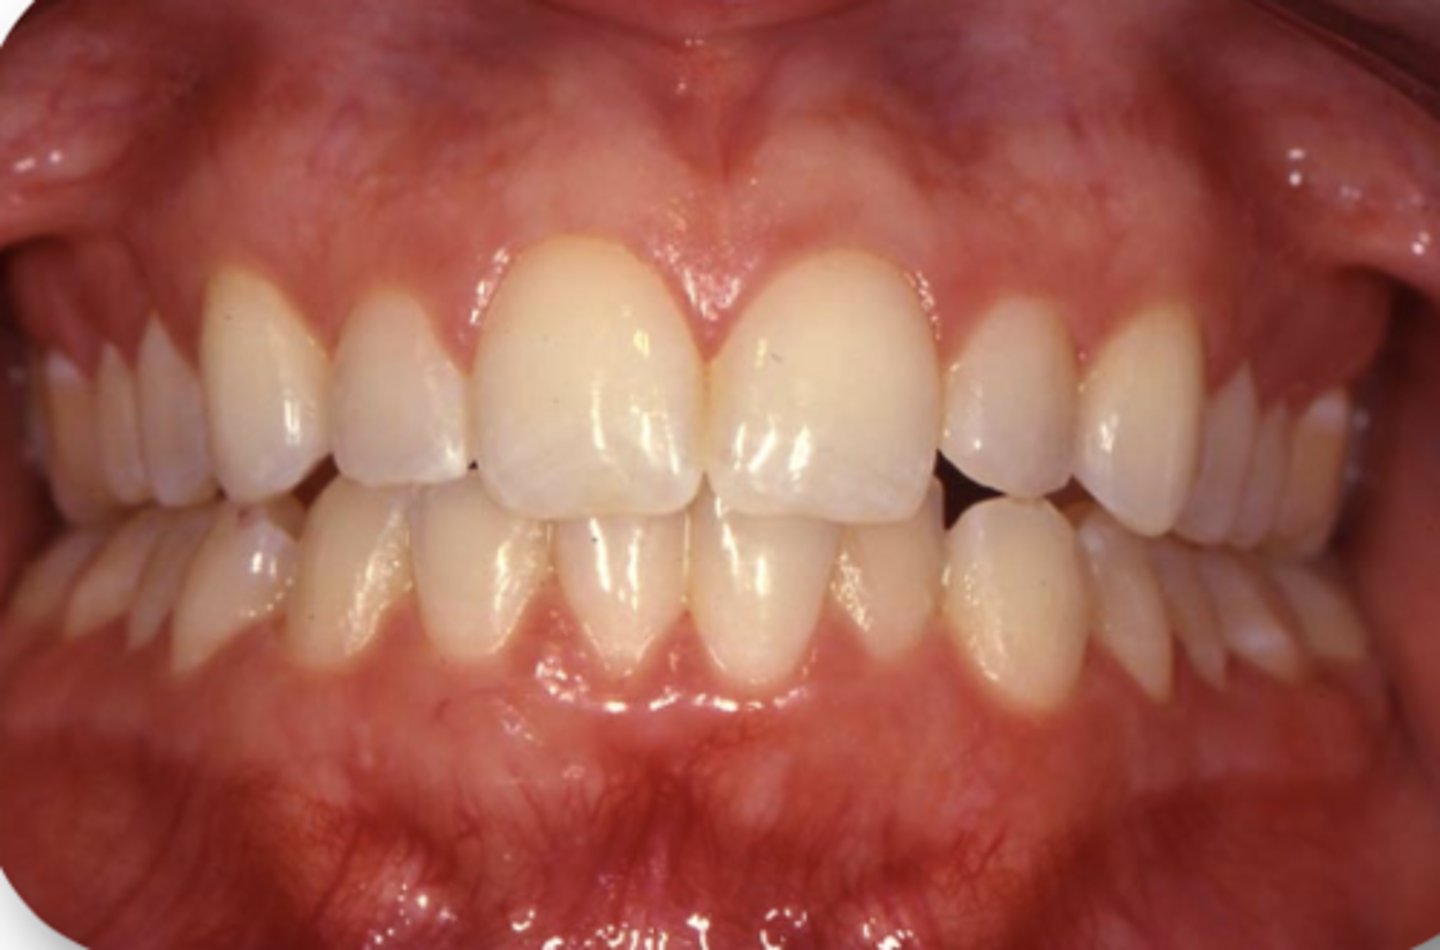

Class I

ID the classification of prosthodontic diagnostic index:

Ideal or minimally compromised

May be treated and experience satisfactory results with conventional, complete dentures

How can you treat patients with a class I prosthodontic diagnostic index?